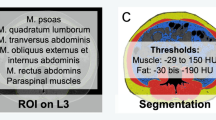

Skeletal muscle mass and fat tissues were measured using stored images from CT performed prior to any treatment, as previously described [7]. Skeletal muscles and visceral and subcutaneous fat areas were assessed from a single axial slice at the third lumbar (L3) level [14]. Hounsfield unit (HU)-based analysis of images was performed using dedicated SliceOMatic software (version 4.3; TomoVision, Montreal, Canada) to segment fat and lean tissue and quantify the cross-sectional area of each tissue type by totaling the given pixels of a tissue and multiplying that sum by the absolute unit pixel surface area (Supplemental Fig. 1). The following parameters were assessed: skeletal muscle mass including the mass of the psoas, quadratus lumborum, transversus abdominis, external and internal obliques, rectus abdominis, and erector spinae muscles; subcutaneous fat mass including the fat present in the subcutaneous tissue; and intramuscular fat contained in intercostal muscles and visceral fat mass. The fat present in the psoas was not considered for the assessment of adiposity. CT attenuation thresholds were − 29 HU to 150 HU for skeletal muscles and − 190 HU to − 30 HU and − 50 HU to − 150 HU for subcutaneous and visceral adipose tissues, respectively. Adipose tissue was taken as the sum of subcutaneous and visceral adipose tissues. This value was normalized for stature to calculate the lumbar L3 skeletal muscle index (SMI) and lumbar L3 adipose tissue index (ATI).

Supplementary Figure 1

(PDF 434 kb)